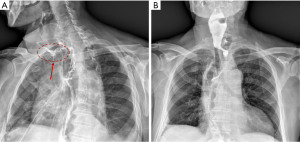

Several risk factors are involved in the development of anastomotic leakage, like: surgical technique and expertise, location of the anastomosis, preoperative radiotherapy, malnutrition, diabetes and corticosteroid use (24). Mechanical anastomoses with linear stapler seem to be associated to less risk of fistula and stricture compared to manual ones (27,28); cervical localization is also associated to a higher risk of leakage (29,30) but to lower mortality and can be managed by opening the cervical incision (Figure 2A,2B).